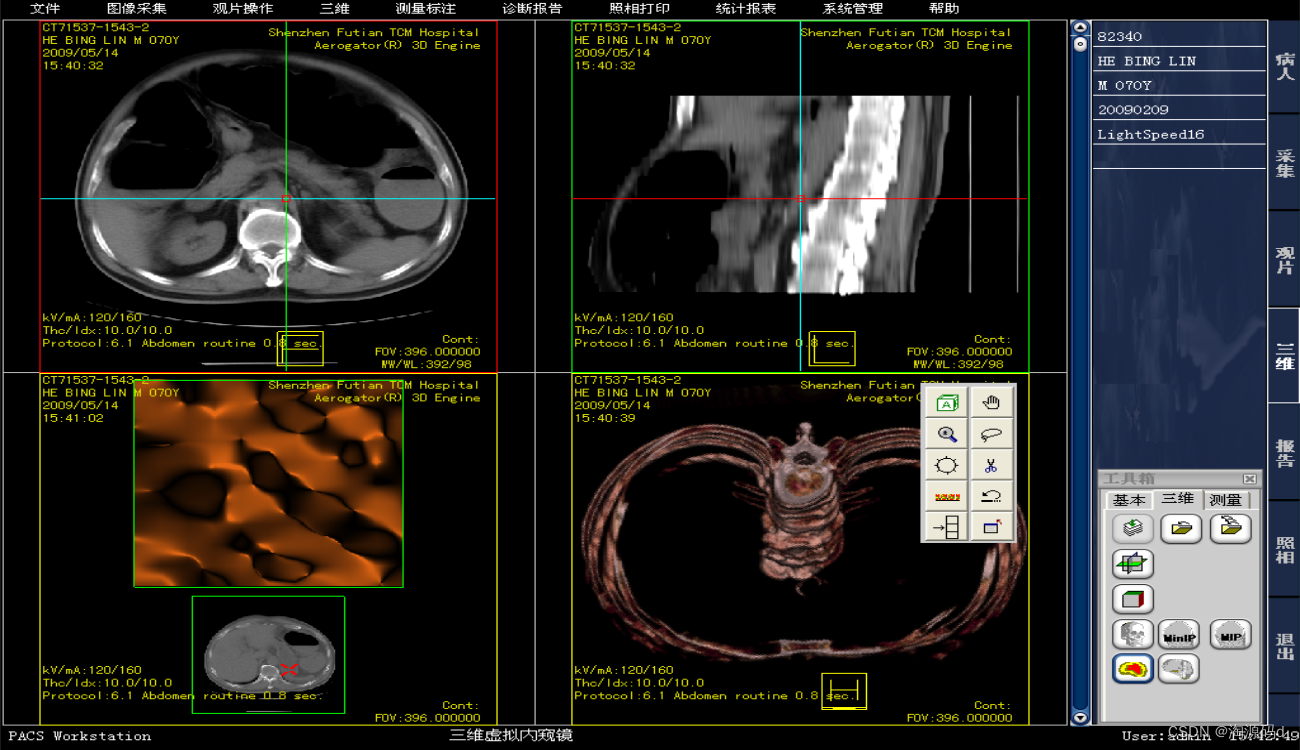

图像浏览及3D后处理系统

图像显示

亮度/对比度调节,窗宽/窗位调节;

单幅/多幅显示,同步操作;

缩放、局部放大;

图像移动、旋转、镜像、反像显示。

测量标注

CT值测量;

长度、角度、矩形、椭圆、曲线任意面积测量;

自定义显示DICOM标注信息;

定位线显示。